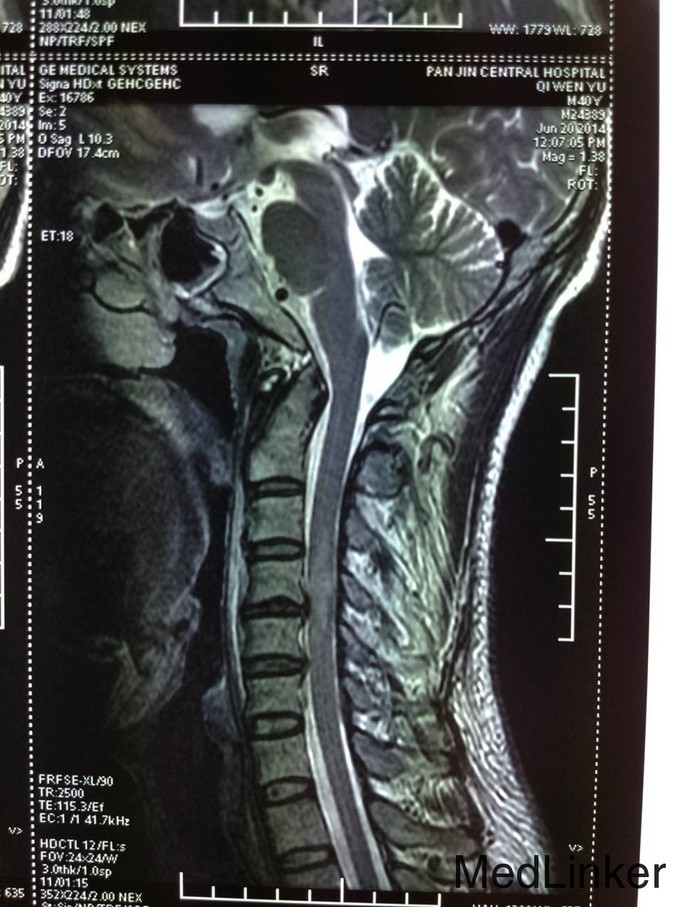

诊断:颈椎外伤(不全瘫);脊髓损伤 患者入院后完善相关检查,查无手术禁忌症后急诊行颈椎后路椎板减压椎管扩大单开门侧块螺钉内固定术,术后患者生命体征平稳,双上肢感觉疼痛,双下肢足趾肌力恢复到1级,术后3天后转入康复科继续康复治疗。

患者颈椎外伤不全瘫,应及早的行手术治疗,完善检查后可见MR的脊髓有高信号,应早期减除压迫,恢复神经功能。